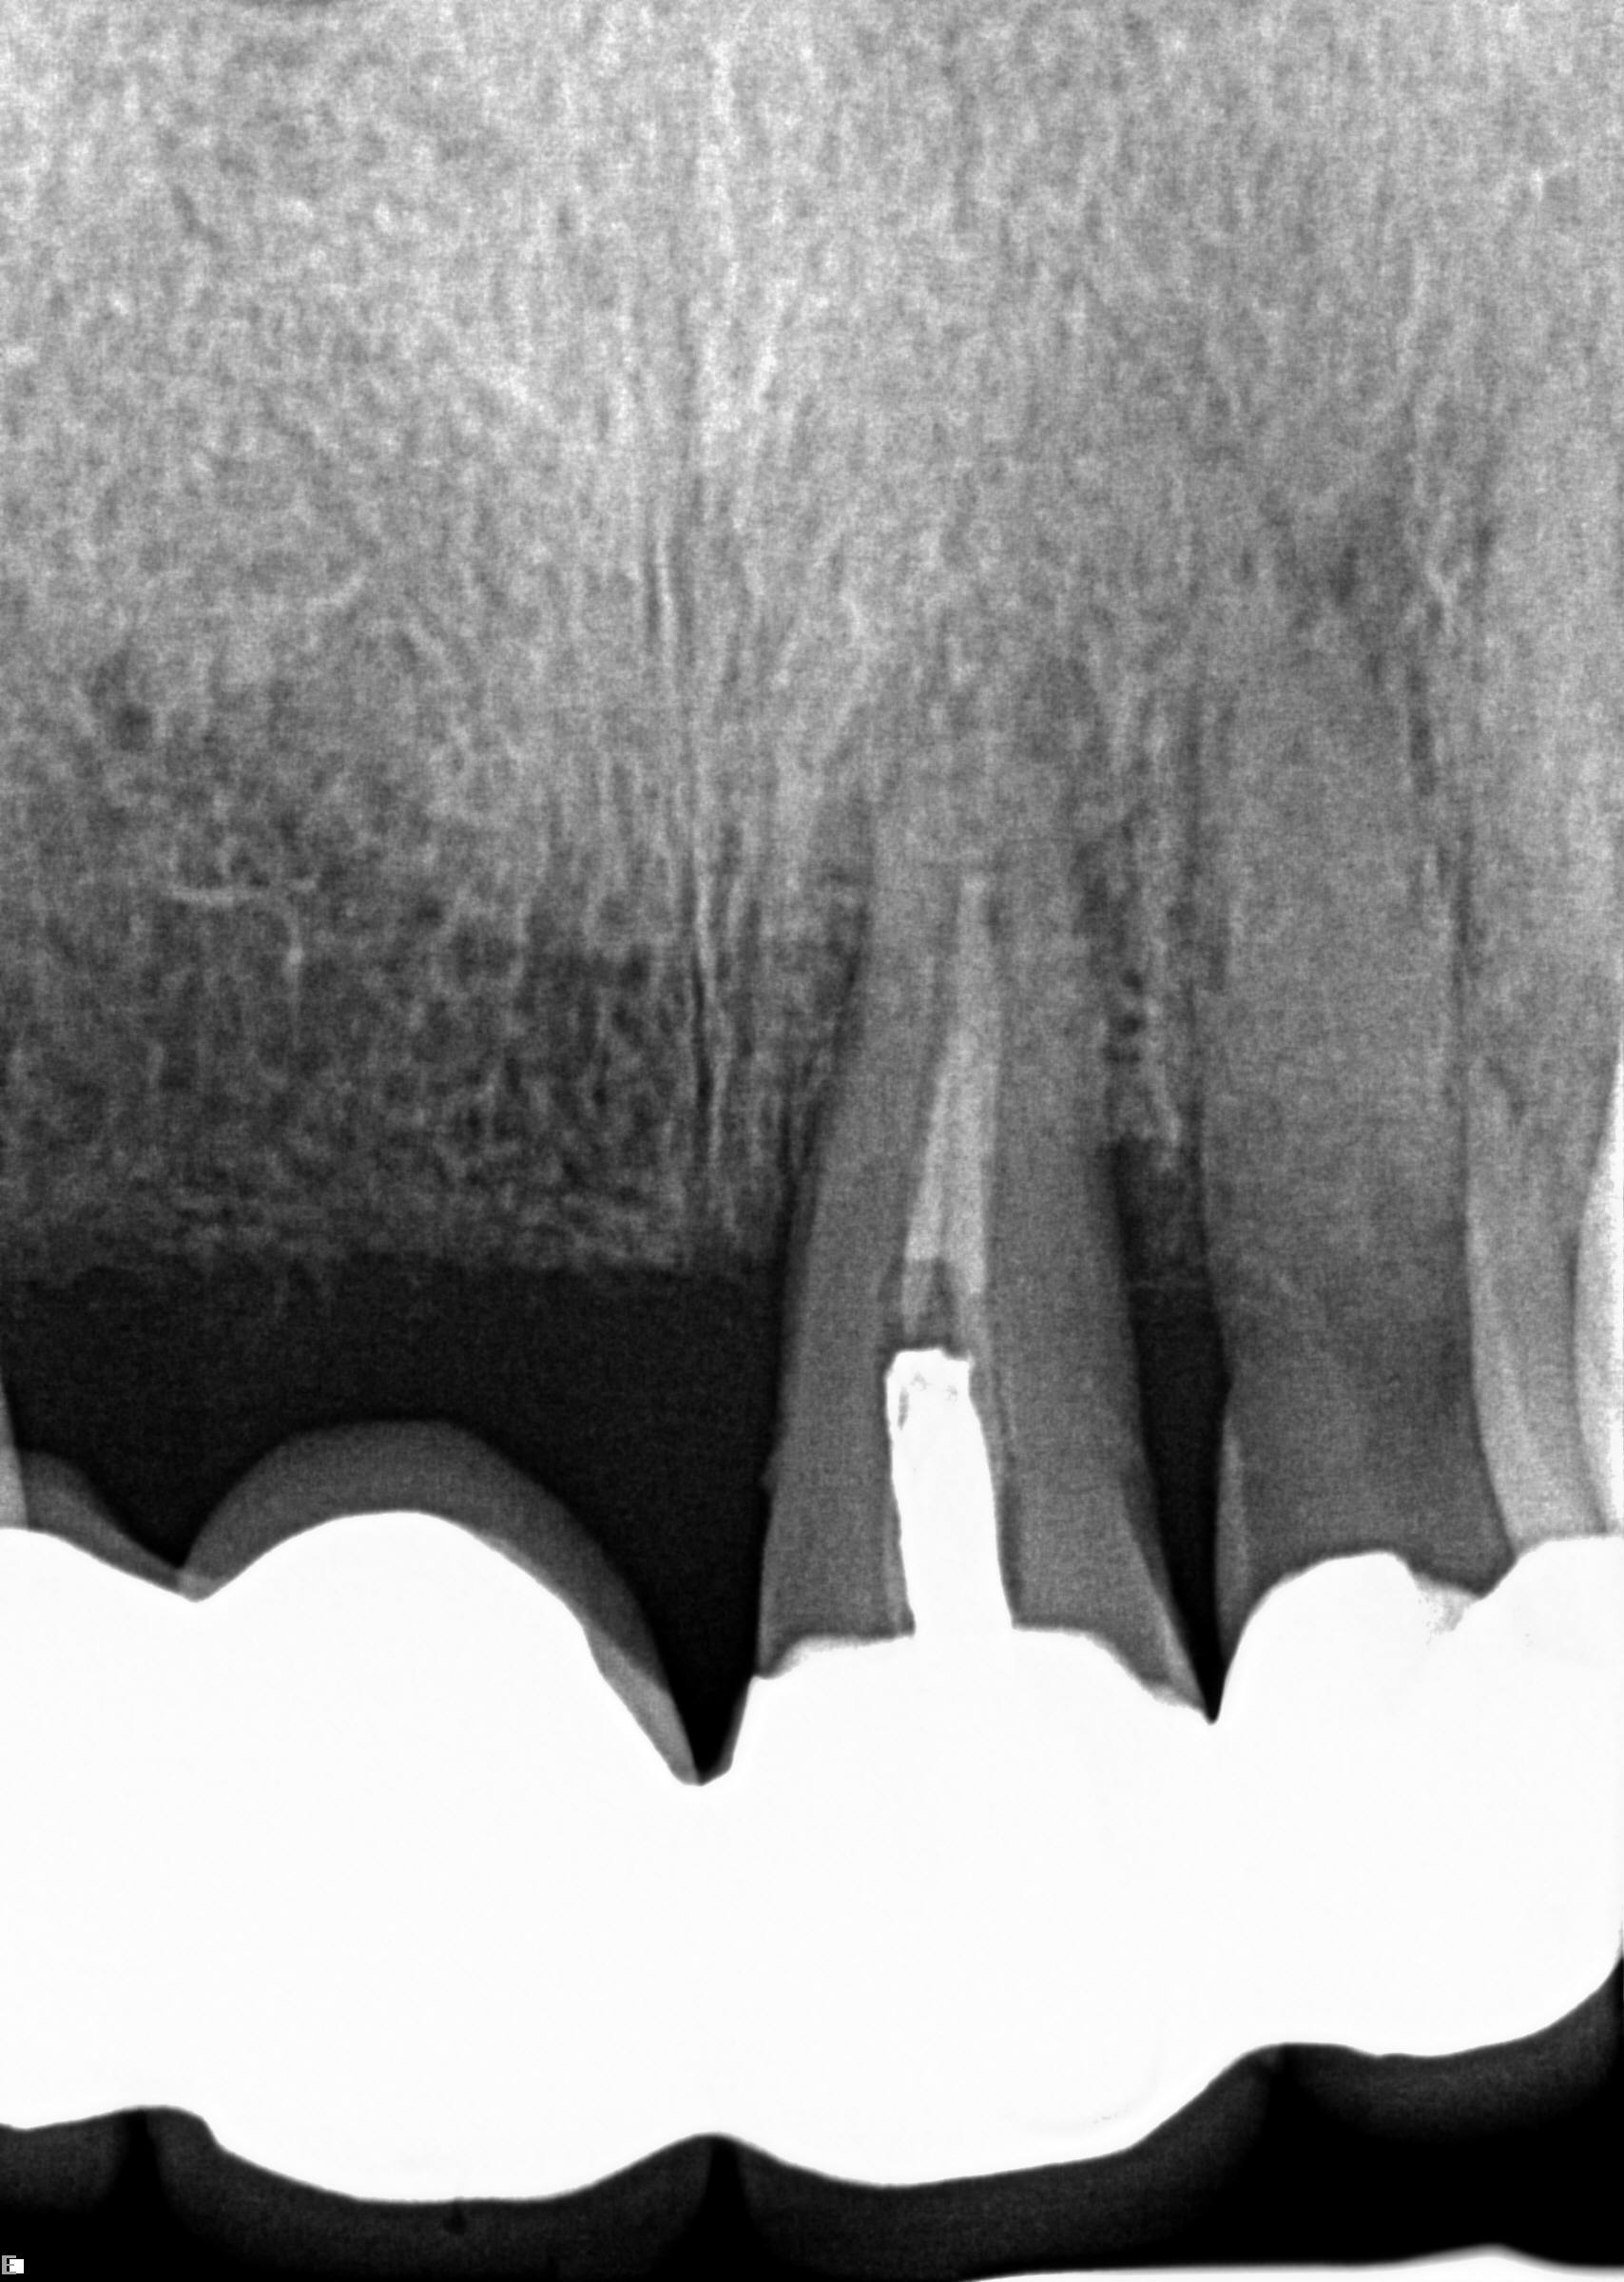

(1.) Case 1 initial radiograph of No. 19.

Figure 1

A 63-year-old woman presented with severe pain on biting of tooth No. 19 (Figure 1). Clinically there was pain on percussion and significant periodontal probing along the mesial root. The patient was anesthetized with infiltration anesthesia and the crown was horizontally sectioned from the lingual of the tooth. The remaining tooth was sectioned so the roots could be extracted individually. The socket was fully debrided and an implant was placed (Figure 2), which was prosthetically correct and stabilized in excess of 45 Ncm. The bone was milled to allow for unimpeded placement of a temporization abutment. The initial crown was revised to be the temporary crown in infraocclusion. Cement was extruded extraorally (Figure 3) prior to seating of the temporary restoration. The socket was sealed with the temporary crown and there were no sutures or bone graft (Figure 4 and Figure 5).